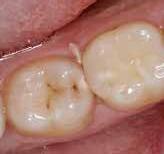

Caries er en ikkesmitsom sygdom i de hårde tandvæv initieret af ubalance, dysbiose, i det orale økosystem og en funktionel modifikation af det dentale mikrobiom. Langvarigt indtag af en sukkerholdig diæt har betydelig effekt på mangfoldigheden i den orale mikrobiota, hvilket reducerer populationen af nogle bakterieslægter og -arter og øger mængden af andre. Syretolererende og syreproducerende bakterieslægter, såsom Streptococcus, Scardovia, Veillonella, Rothia, Actinomyces og Lactobacillus, er biomarkører for sygdommen. Høj sukkereksponering fører til øget metabolisk aktivitet og til funktionelle ændringer i det dentale mikrobiom, hvis rumlige struktur er af afgørende betydning i cariesprocessen. Hos cariesaktive patienter har analyser påvist lokaliserede ”virulens-hotspots” sammensat af flere bakteriearter arrangeret i en coronalignende struktur med en tæt indre kerne af Streptococcus mutans Disse cirkulære hotspots skaber lokaliserede områder med meget lave pH-forhold ved biofilm/tandgrænsefladen, som hurtigt fører til demineralisering af tandens hårdtvæv.

Symbiose og dysbiose

En artsrig oral biofilm med mange forskellige typer af funktionelle bakteriegrupper (cluster) er forbundet med god oral sundhed. Biofilmen er i så fald i symbiotisk balance, hvilket betyder, at den er relativt stabil og modstandsdygtig over for miljøpåvirkninger. De ”gode” streptokokker (Streptococcusmitis, Streptococcus gordonii, Streptococcus sanguinis) dominerer i den dentale biofilm. Der findes også et fåtal patogene bakterier, men de gør ingen skade. Hvis biofilmen udsættes for ydre påvirkninger eller længevarende økologisk stress, forstyrres balancen, og bakteriesammensætningen ændres (5). Dette kaldes dysbiose og kan give anledning til sygdomme med ødelæggende konsekvenser. Caries er et resultat af en sådan pHdrevet dysbiose, som opstår, når et individ igennem længere tid eksponeres for en sød og klæbrig kost uden regelmæssig tandbørstning. Det sure miljø, som opstår i mundhulen, giver en økologisk fordel for syretolerante og syreproducerende bakterier, og andelen af disse øges derfor i den dentale biofilm (Fig. 2). Dette fører til en negativ spiral, hvor de syreproducerende bakterier gradvist indtager uforholdsmæssigt meget plads i biofilmen. Både antallet og andelen af disse mikroorganismer øges samtidig med, at deres funktion i biofilmen ændres. En høj sukkereksponering trigger de syreproducerende bakteriers metaboliske aktivitet og forøger deres evne til at nedbryde sukker og stivelse fra kosten (6). Dette øger efterfølgende produktionen af syrer, som giver en sænkning af mundhulens pH-værdi, hvilket fører til demineralisering af emaljen og udvikling af caries.

Virulens-hotspots